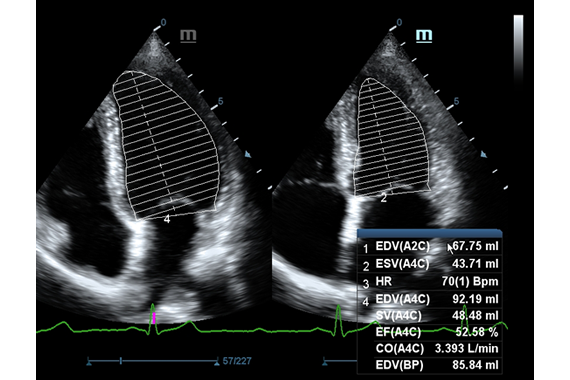

• Кардиология